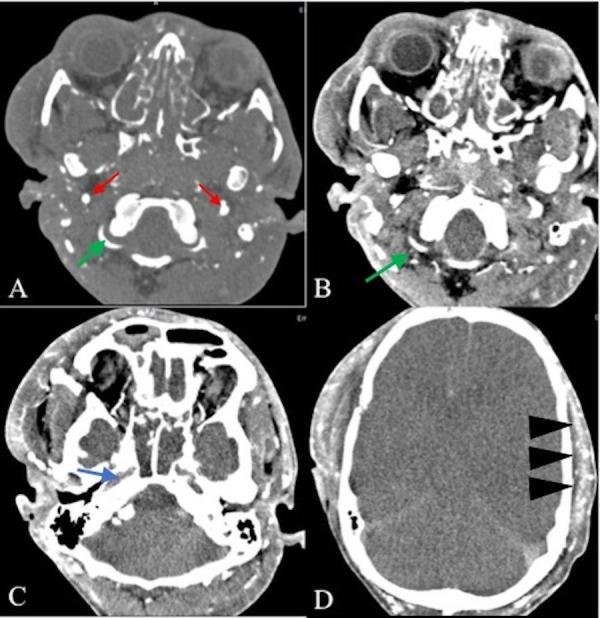

Introduction Brain death (BD) is the irreversible termination of the functioning of the brain. The diagnosis should be first made by clinical criteria and confirmed by using paraclinical confirmatory techniques (ancillary tests). While conventional brain angiography remains the standard method of choice, computed tomography angiography (CTA) has emerged as an alternative method. In this study, we tried to evaluate the accuracy of CTA for the diagnosis of BD. Methods In this study, we included nine patients with a clinical diagnosis of BD, confirmed by electroencephalography (EEG). CTA was then performed to compare the results. Results The most frequent cause for BD was multiple trauma (7/9) in our patients, followed by aneurysm rupture and brain infarct. CTA examination in all patients showed opacification of extracranial arteries and major branches of external carotid artery (ECA), including superficial temporal arteries (STAs), while no opacification was observed in the internal carotid arteries (ICA) including and beyond the cavernous segment, middle cerebral arteries (MCAs), anterior cerebral arteries (ACAs), distal vertebral arteries (VAs), and basilar artery (BA). Moreover, no opacification was observed in the internal cerebral veins (ICVs) or great cerebral vein (GCV). Conclusion The accuracy rate of CTA in the detection of intracranial circulatory arrest was 100%. CTA examinations confirmed BD diagnoses in all patients who had clinical and EEG BD diagnoses, and no confliction between CTA findings and clinical diagnoses was observed.

在我们的患者中,导致脑死亡最常见的原因是多发性创伤(7/9),其次是动脉瘤破裂和脑梗死。所有患者的CTA检查均显示颅外动脉和颈外动脉(ECA)的主要分支显影,包括颞浅动脉(STA),而在包括海绵窦段及其远端的颈内动脉(ICA)、大脑中动脉(MCA)、大脑前动脉(ACA)、椎动脉远端(VA)和基底动脉(BA)中未观察到显影。此外,在大脑内静脉(ICV)或大脑大静脉(GCV)中也未观察到显影。